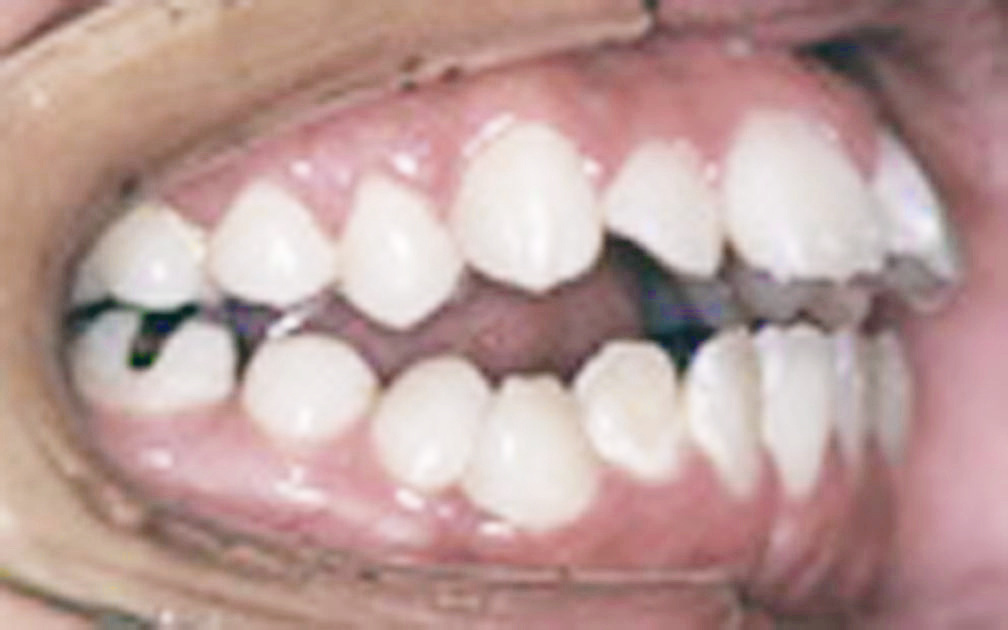

矯正の症例5 (診断名)下顎前突(カガクゼントツ)(外科的矯正有)

(患者様の主訴)前歯で噛めない

(治療開始年齢)28歳0カ月

(主な治療装置)エッジワイズアプライアンス 外科的矯正治療

(抜歯部位)非抜歯

(治療期間)4年7カ月

(治療費)¥266990

(個別リスク・副作用)外科的矯正治療で長期にわたりブラケットを装着しているため齲蝕になるリスクがある。

初診時より低位舌が強いため、矯正治療後に下顎が広がりやすく安定したかみ合わせを得にくいというリスクがある。そのため治療後下顎の幅が広がらないように長期にわたり保定装置を装着する必要がある